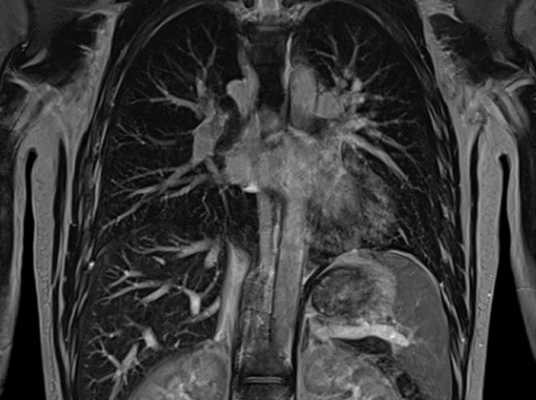

- Магнитно-резонансная томография или компьютерная томография опухоли. Эти исследования позволяют адекватно оценить распространенность опухолевого процесса, прилежание опухоли к магистральным сосудисто-нервным структурам, степень вовлечения прилежащих анатомических структур и как следствие сделать вывод о возможности проведения хирургического лечения.

Диагноз выставляют на основании осмотра, данных инструментальных исследований и результатов биопсии. Пациентов с десмоидной опухолью направляют на УЗИ, КТ и МРТ. Наиболее информативным методом исследования, позволяющим установить границы опухоли и степень ее инвазии в окружающие ткани, является магнитно-резонансная томография. При необходимости назначают ангиографию сосудов и другие исследования. При прорастании сосудов, нервов, внутренних органов и костных структур может потребоваться консультация сосудистого хирурга, невролога, абдоминального хирурга, торакального хирурга, травматолога, ортопеда и других специалистов.

Что показывает МРТ органов грудной клетки

В грудной клетке расположено множество жизненно важных органов, патологии которых сложно диагностировать классическими способами: они скрыты за костями грудины, ребрами, позвоночником, мягкими тканями. Информативным способом, который способен показать структуру, а также функциональность органов, расположенных здесь, врачи называют МРТ — магнитно-резонансную томографию с контрастом или без него. Метод идеально подходит для исследования находящихся внутри грудины органов, сосудов, желез, лимфоузлов, но наиболее эффективным его считают в диагностике опухолевых процессов.

Чтобы понять, что показывает МРТ грудной клетки, важно понимать суть метода. Он состоит в способности мощного магнитного поля провоцировать резонанс молекул водорода, который в больших количествах содержится в органах грудной клетки (сокращенно ОГК). Магнитно-резонансный томограф улавливает резонансные колебания и отображает их на теле-экране в виде серии монохромных снимков, представляющих собой срезы обследуемой области определенной толщины: чем мощнее МР-аппарат, тем «тоньше» срезы и точнее результаты. Также на основе полученных данных можно сделать трехмерную модель любой структуры, находящейся в полости груди.

При использовании контрастного вещества список диагностируемых органов и структур расширяется за счет крупных и мелких кровеносных сосудов. С помощью этого дополнения МР-сканирование показывает не только строение кровеносной сети, но также особенности ее функционирования и изменения в скорости и направлении кровотока. Благодаря тому, что контраст хорошо накапливается в патологических новообразованиях, контрастное МРТ обладает высокой информативностью в диагностике опухолей органов средостения, включая легкие и лимфатическую систему.